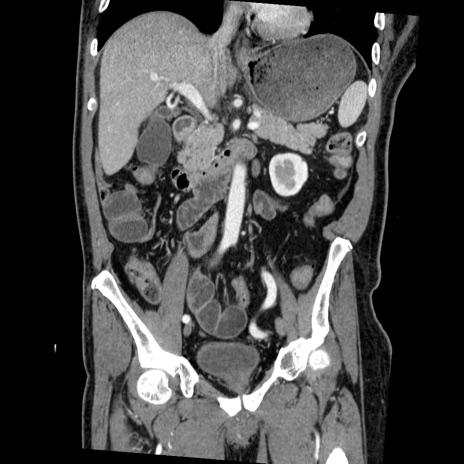

横断像

【症例】50歳代男性

【主訴】腹痛

【現病歴】AVMからの被殻出血のため回復期リハ病棟入院中。 本日午後3時頃急に下腹部痛が出現した。

【既往歴】AVM、被殻出血、虫垂炎、高血圧

【身体所見】意識晴明、左半身不全麻痺、会話の理解は良好、36.5°C、腹部:膨隆、全体に板状硬、下腹部正中に圧痛点あり、反跳痛-、筋性防御不明、右下腹部にope scar

【データ】WBC 9400、CRP 0.06